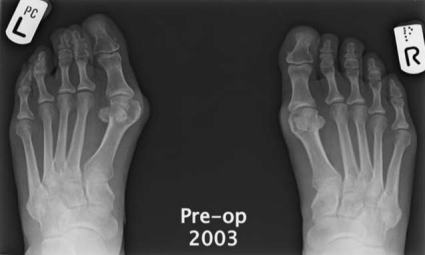

Figure 1

Figure 2

Figure 3

Radiographic evaluation revealed a preoperative mean hallux valgus angle (HVA) of 32.6 degrees (SD = 5.4) and an intermetatarsal angle (IMA) of 14.2 degrees (SD = 3.1), indicating significant deformity and joint involvement. Following the silastic joint replacement arthroplasty, there was a significant improvement in the radiographic measurements. The postoperative mean HVA decreased to 12.8 degrees (SD = 3.6), and the mean IMA decreased to 5.1 degrees (SD = 2.2). These changes were statistically significant (p < 0.001), indicating successful correction of the deformity.